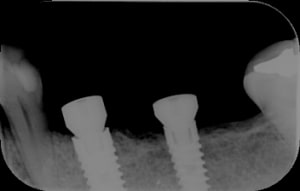

Simulation implantaire assistée par ordinateur pour MCIPE Poditdental 006.jpg

Simulation implantaire assistée par ordinateur pour MCIPE Poditdental 005.jpg

Simulation implantaire assistée par ordinateur pour MCIPE Poditdental 004.jpg

Simulation implantaire assistée par ordinateur pour MCIPE Poditdental 003.jpg

Simulation implantaire assistée par ordinateur pour MCIPE Poditdental 002.jpg

Simulation implantaire assistée par ordinateur pour MCIPE Poditdental 001.jpg